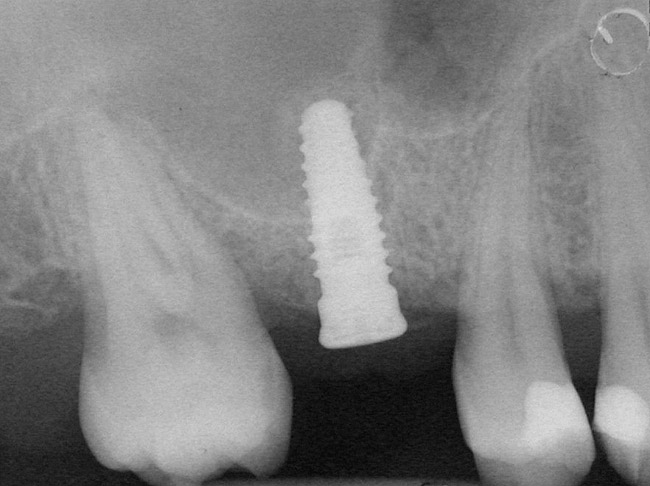

Case 2

A 55-year-old male was referred for implant placement and prosthetic rehabilitation in the area of tooth No. 15. The tooth had been extracted 4 years prior. The radiograph revealed inadequate bone height for implant positioning (Figure 6). It was decided to insert an implant that was 11.5 mm in length and 3.75 mm in diameter, performing a slight osteotomic maxillary sinus lift. A heterologous bone graft also was planned to obtain a larger sinus lift.

A full-thickness mucoperiosteal flap was raised, and alternating osteotomes were used to prepare the implant site. After achieving a length of 7 mm (Figure 7A and Figure 7B), heterologous bone graft was implanted and the osteotome sequence was repeated. The implant showed primary stability.

Second-stage surgery was performed after 4 months (Figure 8); healing abutments were placed and the soft tissue was allowed to heal for 5 more weeks. Then, splinted porcelain-fused-metal (PFM) crowns supported by custom gold abutments were delivered (Figure 9 and Figure 10).

Figure 8  At 4 months after treatment, the radiograph revealed the presence of a bone layer surrounding the implant.

Figure 8